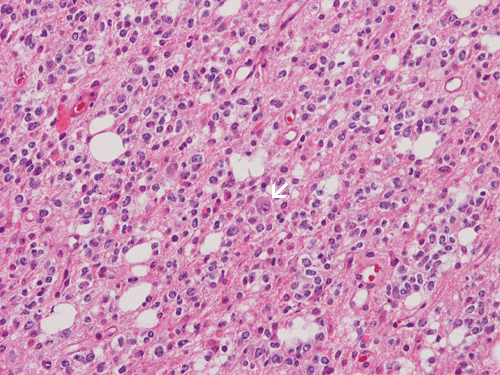

Answer and Discussion: The answer is (B). The tumor being shown here is most consistent with an oligodendroglial tumor. The image being shown here is obtained form an oligodendroglioma, WHO grade II. characterized by delicate blood vessel network, rather monotonous and round nuclei, and perinuclear halo. Note that there is an entrapped neuron (arrow) at the center of the lesion. This is a testimony to the invasive nature of this tumor. These tumors often have mutation of IDH. A lost of chromosome 1p and 19q can be seen in some of the cases and indicate responsiveness to chemotherapy.

Oligodendroglial tumors can be positive for GFAP and can have minigemistocytes. Both of them are not diagnostic, however. Some of them also have positivity for synaptophysin. However, when the immunoreactivity for synaptophysin is strong and that the tumor is close to the ventricles, a possibility of central neurocytoma should be considered.

Pilocytic astrocymoa often have BRAF-KIAA1549 fusion. Some of them may also have nuclear halos which raise the suspicion of an oligodendroglioma. However, the age and location of this tumor does not suggest pilocytic astrocytoma. Also, there is no classic histologic features suggestive of a pilocytic astrocytoma here. Also, the entrapped neurons within tumor cells is not a common feature of pilocytic astrocytoma which is non-invasive and well demarcated in most cases.